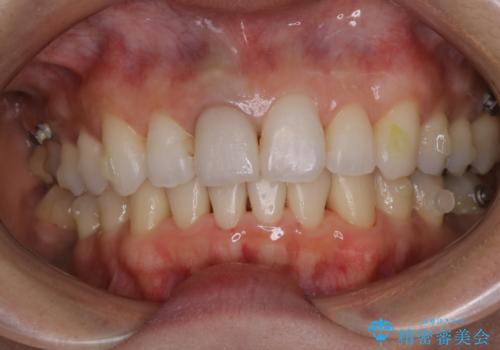

- インビザラインでのマウスピース矯正中にステインや着色を取りたいとのことでした。

PMTC60分コースを行いました。

PMTC(保険外治療)は、毎日の歯磨きで落としきれない汚れや、コーヒ、紅茶・タバコのヤニなどの着色も除去します。目には見えない歯と歯の間・歯肉の境目・インビザライン中はアタッチメント周囲などに残っているプラーク(歯垢)もしっかり取り除きます。PMTCでは専門的な機械や材料を使用して、徹底的に汚れを除去するため、虫歯・歯周病・口臭予防などにつながります。

またPMTCを行うことで、ご自身本来の歯の色になり自然な明るさになります。